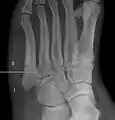

For several reasons, a Jones fracture may not unite. The diaphyseal bone (zone II), where the fracture occurs, is an area of potentially poor blood supply, existing in a watershed area between two blood supplies. This may compromise healing. In addition, there are various tendons, including the peroneus brevis and fibularis tertius, and two small muscles attached to the bone. These may pull the fracture apart and prevent healing.

Zones I and III have been associated with relatively guaranteed union and this union has taken place with only limited restriction of activity combined with early immobilization. On the other hand, zone II has been associated with either delayed or non-union and, consequently, it has been generally agreed that fractures in this area should be considered for some form of internal immobilization, such as internal screw fixation.

These zones can be identified anatomically and on x-ray adding to the clinical usefulness of this classification.[18] Surgical intervention is not, by itself, a guarantee of cure and has its own complication rate. Other reviews of the literature have concluded that conservative, non-operative, treatment is an acceptable option for the non-athlete.[19]

Anatomy of the fifth metatarsal.